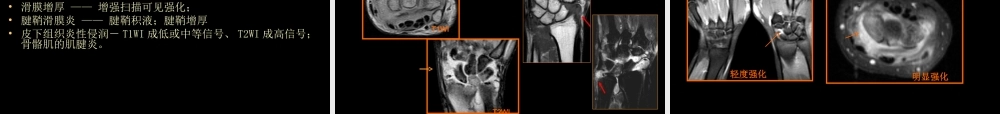

类风湿性关节炎、强直性脊柱炎影像学诊断中国石油中心医院杨景震内容附:Reiter's综合征一、类风湿性关节炎二、强直性脊柱炎类风湿性关节炎(rheumatoidarthritis,RA)•自身免疫性疾病,以侵犯关节滑膜为主要特征的炎症性、系统性结缔组织病•主要侵犯四肢,特点为多发性和侵蚀性慢性关节炎•病因至今不明病理•主要病变在滑膜,作为本病的早期、基本的病变•滑膜充血、水肿及渗出、白细胞侵润、滑膜增厚•血管翳:绒毛样的富含血管的肉芽组织•关节软骨变性、破坏•软骨下骨质破坏类风湿病理过程示意图早期24、5361正常;2滑膜肿胀,周围软组织水肿;3滑膜增厚累及关节软骨,血管翳形成;4、5累及骨质;6关节强直。富含毛细血管的血管翳覆盖在关节软骨上,并逐渐侵蚀破坏关节软骨,同时刺激软骨下骨,使骨质发生充血水肿和不规则溶解。冠状面将关节分为正常与病变各半的对比示意图被滑膜“吃掉”的软骨(黄箭)保留的关节软骨(蓝箭)术中所见临床表现•25-50岁女性发病率高于男性•好发部位是近侧指间关节、掌指关节和腕关节•僵硬感,关节肿胀、交替性关节疼痛,功能受限•附近软组织挛缩,关节半脱位•类风湿因子阳性:70%血清中可有类风湿因子(RF)。RF是滑膜中淋巴细胞和浆细胞产生的一种免疫球蛋白,有lgM、lgG、和lgA三类,其中又以lgM类含量多,故目前多测定lgM类风湿因子。RF阴性不一定就不是类风湿,因为其可被其他血清蛋白所掩盖,或由于在血清中被有高度亲和力的抗体结合,所以检验不出来。早期的软骨侵蚀晚期的软骨及骨破坏软组织肿胀晚期的畸形类风湿关节炎的影像学检查方法•X线、CT扫描、超声和MRI扫描等;•传统的X线片显示出的病变多为RA较晚期的改变,特异性不强;•CT扫描对于RA的滑膜及软骨病变的显示能力差;•超声可显示滑膜和腱鞘的改变,不宜评价骨骼的病变•核素扫描及ECT也有表现,不常用。类风湿关节炎的影像学检查方法•MRI对组织分辨率高,基本上可以显示RA的全病程的病理改变,是检查早期RA、观察治疗效果可靠的方法之一MRI检查讲究的方法是:平扫:T1WI、T2WI压脂增强(压脂):打药5分钟内扫描,观察滑膜强化;30分钟,渗出液强化达高峰并持续1h(各个序列依据病变需要,采取多方位)腱鞘:是包围在肌腱外面的鞘管,存在于活动性较大的部位,如腕、踝、手指和足趾等处。腱鞘可分纤维层和滑膜层两部分。腱鞘的纤维层又称腱纤维鞘,它位于外层,为深筋膜增厚所形成的纤维性管道,它起着滑车和约束肌腱的作用。腱鞘...